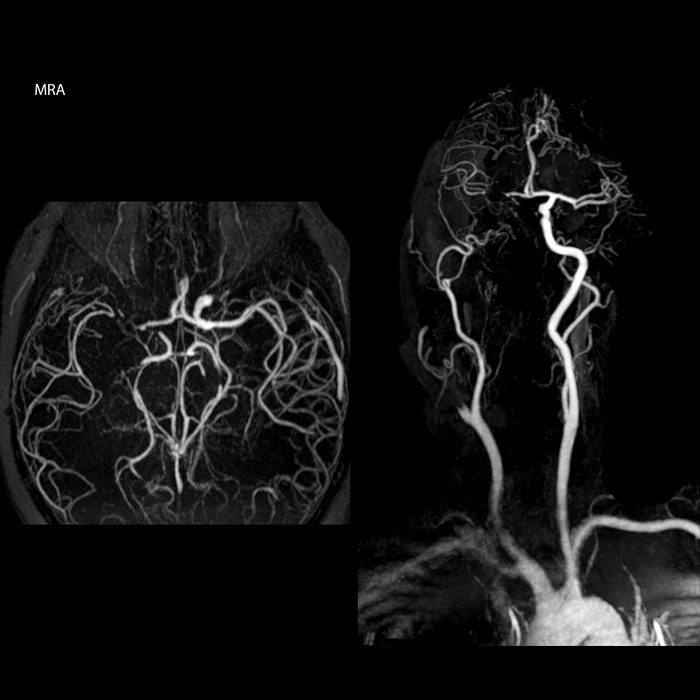

“In France, every stroke is usually imaged with MRI, not CT, even for emergency treatment.” “In France, stroke is usually imaged with MRI, not CT, even for emergency treatment. This is because MRI helps us directly visualize ischemia in the acute phase, but can also help rule out differentials such as MS and hematoma. In addition, we can assess the intracranial and extracranial vessels during the same examination,” says Dr. Savatovsky.

The first challenge in MRI of stroke is speed. The patient typically arrives from an ambulance in the MRI preparation room and the installation is done on a separate dock outside the scanner room. “The venous access is placed during the neurological examination. If the delay from the first symptoms allows the patient to receive thrombolysis we do a very fast examination that typically lasts about 11 minutes including the pre-scans. In the case of transient ischemic stroke we usually add ASL perfusion because in some symptoms with negative diffusion, ASL sometimes indicates a vascular origin.”

“Ingenia provides great flexibility in the parameters setting. We can tune a sequence the way we want,” says Dr. Savatovsky. “For example, in a stroke exam we use a FLAIR sequence of about two minutes instead of the four-minute FLAIR we use for MS. The diffusion is 30 seconds, the T2*-weighted scan is 30 seconds, the angiography scan time is less than one minute. Ingenia is a great scanner in that situation; even with these fast sequences we can achieve good images with good SNR. When the first sequence tells us that it’s not an ischemic stroke but a hemorrhagic stroke, we may switch to a time-resolved angiography to look for vascular malformations and venous thrombosis.

“Every center is different, but for me the ideal protocol for stroke includes diffusion weighted imaging, FLAIR, and fast susceptibility imaging,” says Dr. Savatovsky. “Our fast susceptibility weighted imaging takes 50 seconds, so it’s as fast as T2*-weighted imaging. It visualizes hemorrhage but also the clots. We also do 3D MR angiography that provides information on cervical and brain vessels. If the patient does not need immediate treatment, or if additional information is needed to decide on treatment, we might also add perfusion imaging and post-contrast T1-weighted imaging.”